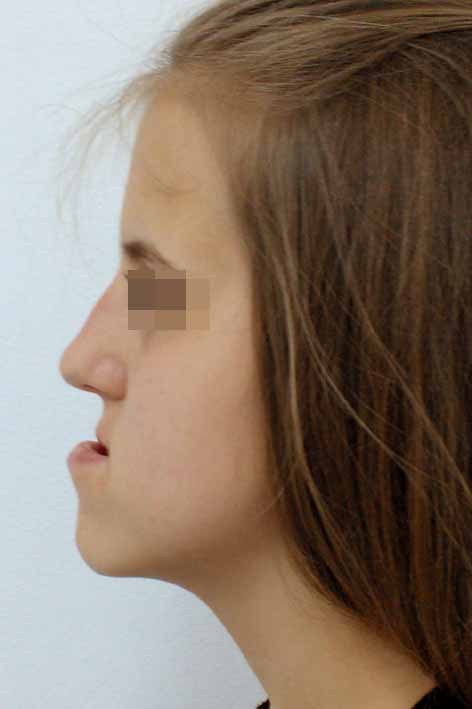

Корекция на брадата преди и след лечението – случай на доц. Джоров